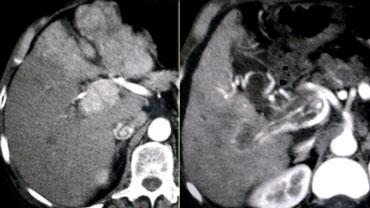

Late appearance of HCC

HCC là một khối u thầm lặng, vì vậy nếu bệnh nhân không có xơ gan hoặc viêm gan C, bạn sẽ phát hiện chúng ở giai đoạn muộn.

Chúng thường có kích thước rất lớn với hình ảnh khảm, vỏ bao, xuất huyết, hoại tử và thoái hóa mỡ.

HCC trở nên đồng tỷ trọng hoặc giảm tỷ trọng so với gan trong thì tĩnh mạch cửa do hiện tượng thải thuốc nhanh.

Trên các hình ảnh thì muộn, vỏ bao và đôi khi các vách ngăn thể hiện sự ngấm thuốc kéo dài.